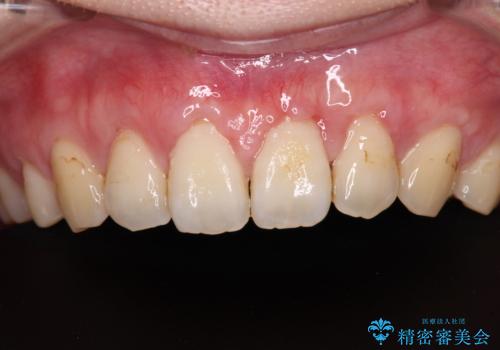

- 他院で矯正治療を終えた結果、上顎前歯の歯肉が退縮してしまい、根が見えていることが気になるとのことで来院された患者様です。

歯肉退縮に対して、上顎からの結合組織移植術(CTG)により、歯根の被覆を行うとともに、歯肉の厚みを増すことで将来の退縮リスクを抑制することとしました。